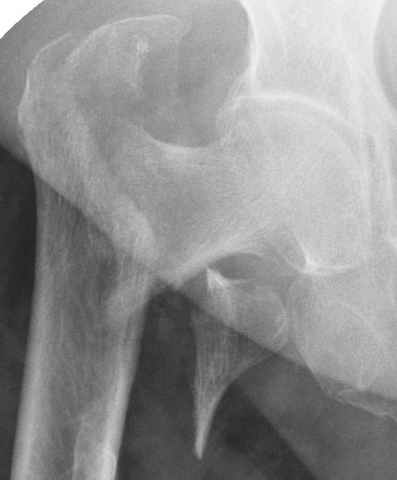

Уважаемые коллеги.Ко мне обратился мой коллега, весьма опытный травматолог, владеющий практически всеми видами остеосинтеза, с просьбой собрать мнения по поводу нескольких клинических случаев - два перелома бедра и перелом плеча.Если можно, подтвердите свое мнение иллюстрациями аналогичных ситуаций, либо ссылками - для клинического разбора. Бедро 1:Женщина 1929 г.р. Травма в результате падения 14.09.04г.Диагноз Закрытый оскольчатый чрезвертельный перелом правой бедренной кости со смещением отломков.Сопутствующие заболевания: ИБС, стенокардия напряжения, постинфарктный кардиосклероз (ИМ в 1992 году); гипертоническая болезнь 2 ст.; ожирение 3. Дополнительные данные - сохранная старушка.Спасибо.С уважением Александр Артемьев

Типичный остеопорозный вертельный перелом , не стабильный, 4-х фрагментный, базоцервикальный. Лечение оперативное не позднее 48 часов после перелома, чем раньше тем лучше, если общее состояние позволяет.

Ap pelvis Rt sub-intra trochanteric Fracture, AP Rt hip, Postop Blade Fixation